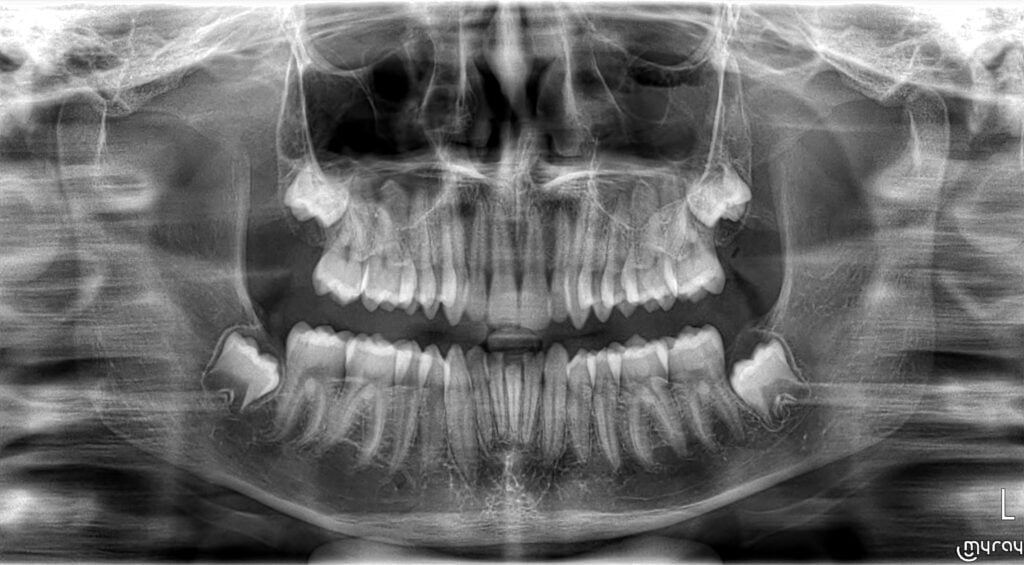

Cette étape est tout aussi importante que le traitement en lui-même, afin d’éviter la récidive de dysmorphose. Le Dr Audrey BAEUMLIN veillera à surveiller la stabilité des résultats, tant au niveau de l’alignement des dents, que sur leur emboitement. Il faudra aussi veiller à la bonne évolution des dents de sagesse, ou alors préférer les faire avulser si leur place d’évolution est insuffisante.